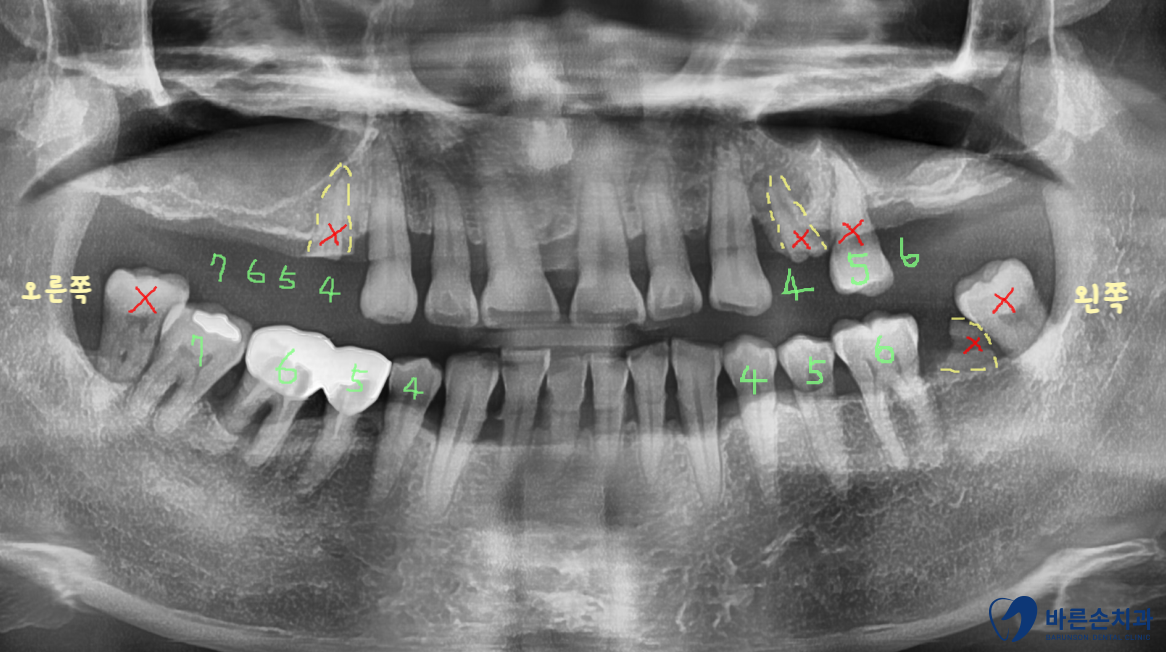

구내 엑스레이 사진을 보면 양쪽 위 어금니들이

빠진지가 오래되어 상악동 함기화가 되어

임플란트 식립할 뼈가 부족합니다.

X 표시가 되어있는 치아는 발치하고

왼쪽은 치아 3개, 오른쪽은 치아 4개를 만들기로 계획을 세웁니다.

왼쪽도 원래라면 4개의 어금니가 전부 있어야 하지만

아래 맞닿는 치아 하나가 어차피 없기 때문에

3개까지만 제작하기로 했습니다.